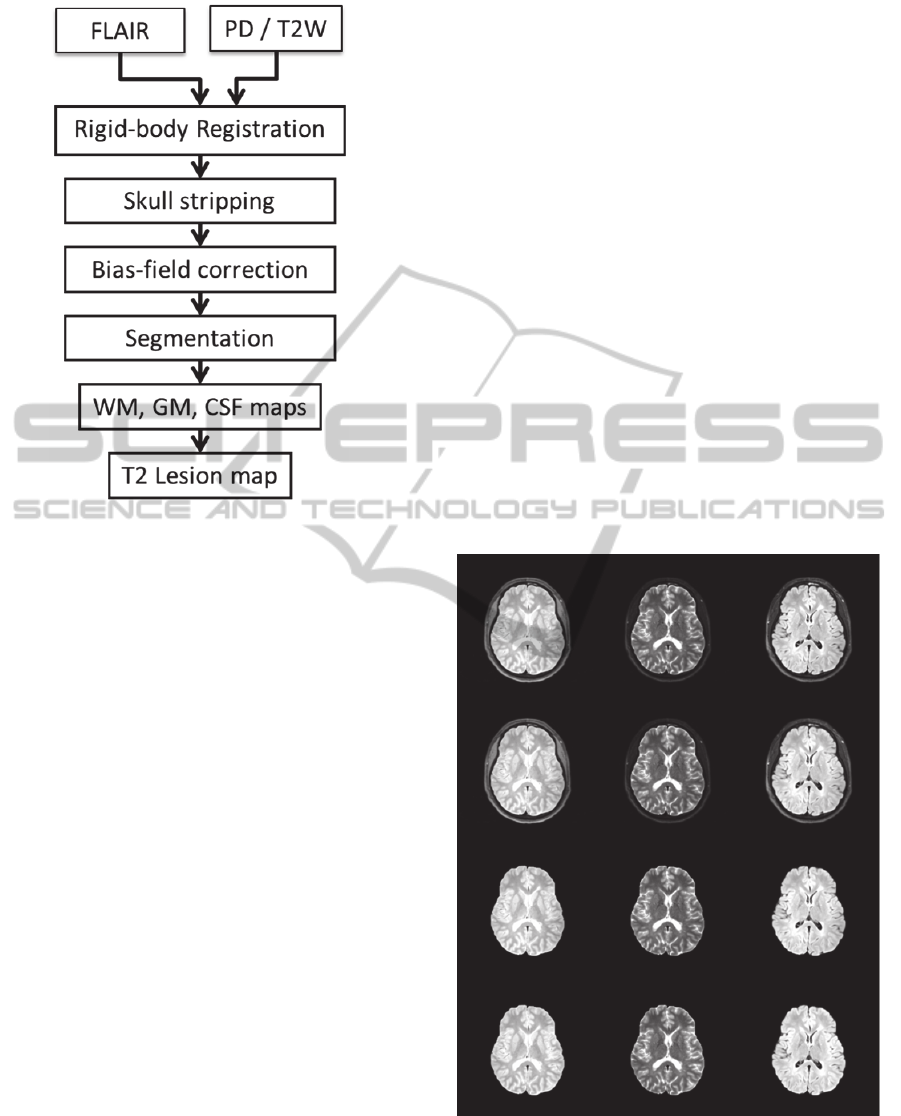

Figure 4: Segmentation results showing masks of white

matter (top left), grey matter (top right), CSF (bottom left),

and WM lesions (bottom right) corresponding to the slice

shown in Fig. 3.